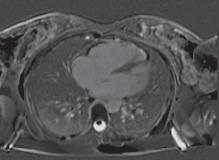

A. Ventrículo direito (VD) com volumes moderadamente aumentados e função sistólica diminuída (fração de ejeção em 3D = 33%), com hipocinesia da parede livre e da câmara de saída do ventrículo direito (CSVD), com pequenas zonas de discinesia (bulging) a nível da parede livre; B. RT a nível da parede livre do VD e CSVD, que pode corresponder a áreas de fibrose.

Figura 22.22 – Ressonância magnética. Figura amavelmente cedida pelo Dr. Nogueira da Silva (Serviço de Cardiologia do Hospital de Santa Marta, Centro Hospitalar de Lisboa Central). A B